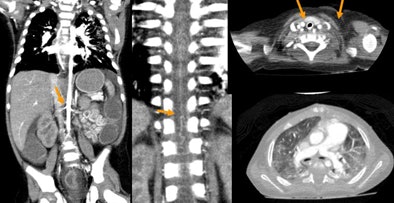

| Newborn with aortic hypoplasia and renal artery stenosis. Weight of 1.7 kg; single-rotation 320-detector-row scan at 0.5 sec, 80 kV, 40 mA, and dose of 0.3 mSv. All images courtesy of Dr. Patrik Rogalla. |